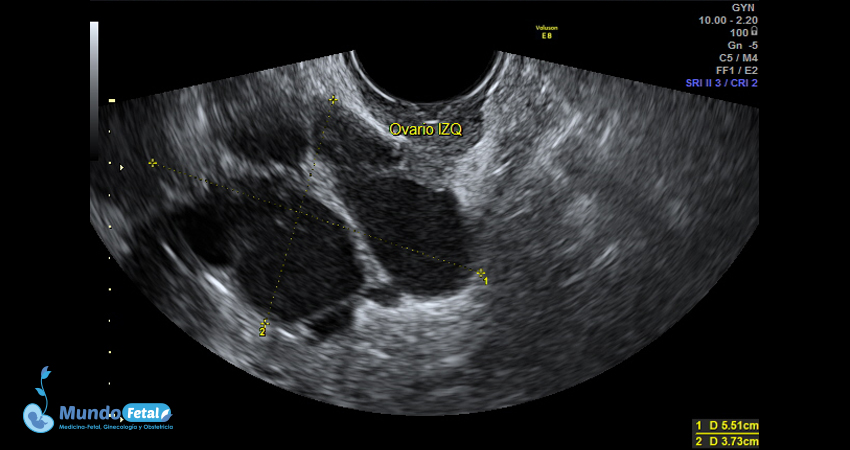

Ultrasonido Pélvico

Estudio anatómico de la región pélvica, que brinda información precisa de (vagina, cérvix, útero, endometrio, trompas de Falopio, ovarios y sus tejidos anexos) de cada uno, descartando alguna complicación de estas estructuras.